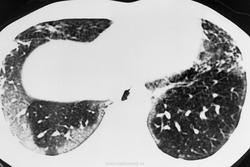

Отравления при вдыхании параквата.

Паракват - это гербицид, который используется в сельском хозяйстве во многих странах.